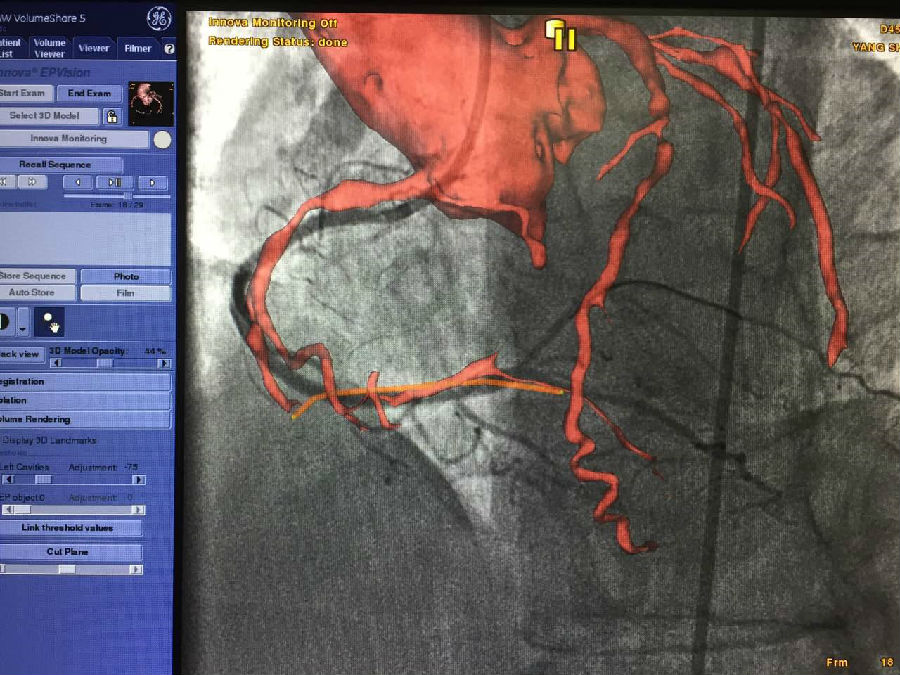

3、冠脉CTO介入融合功能 冠脉CTO病变患者往往会因为冠脉闭塞的时间久、病变的长度长以及严重钙 化导致开通困难,传统的顺行法再通成功率仍不理想,有时通过侧枝血管采取逆行导丝技术处理CTO病变,因此需要特别辨识侧枝血管的开口。 GE 心脏高级解决方案可依据患者术前冠脉CTA 提取主动脉、冠状动脉、侧枝血管的3D模型,并对血管开口进行标记,规划狭窄或闭塞段路径,术中实时引导CTO开通术,提高手术精度。

具体操作步骤如下: 术前提取主动脉及冠状动脉3D模型,规划狭窄或闭塞段路径

(2)术中智能3D实时引导CTO开通,融合影像与心跳/呼吸同步--可精确引导,降低风险,减少造影剂的用量,缩短手术时间